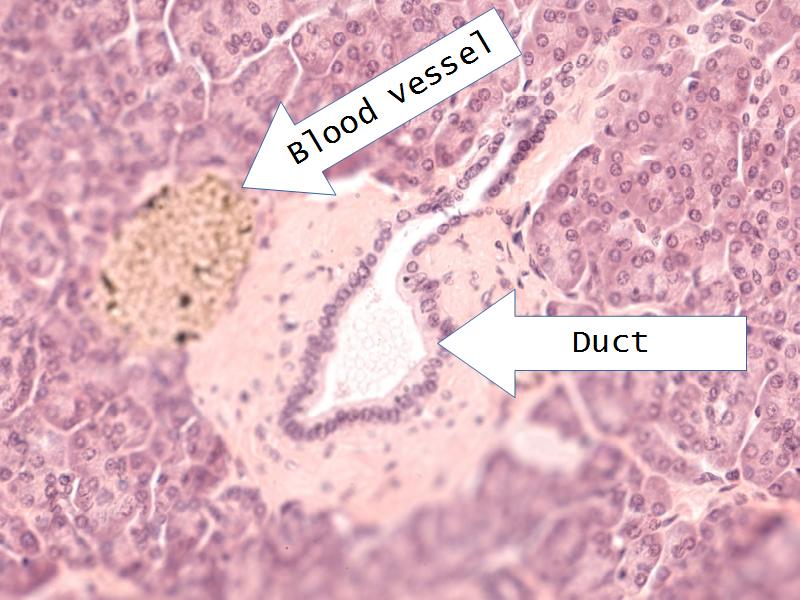

- Slide 76: Kidney